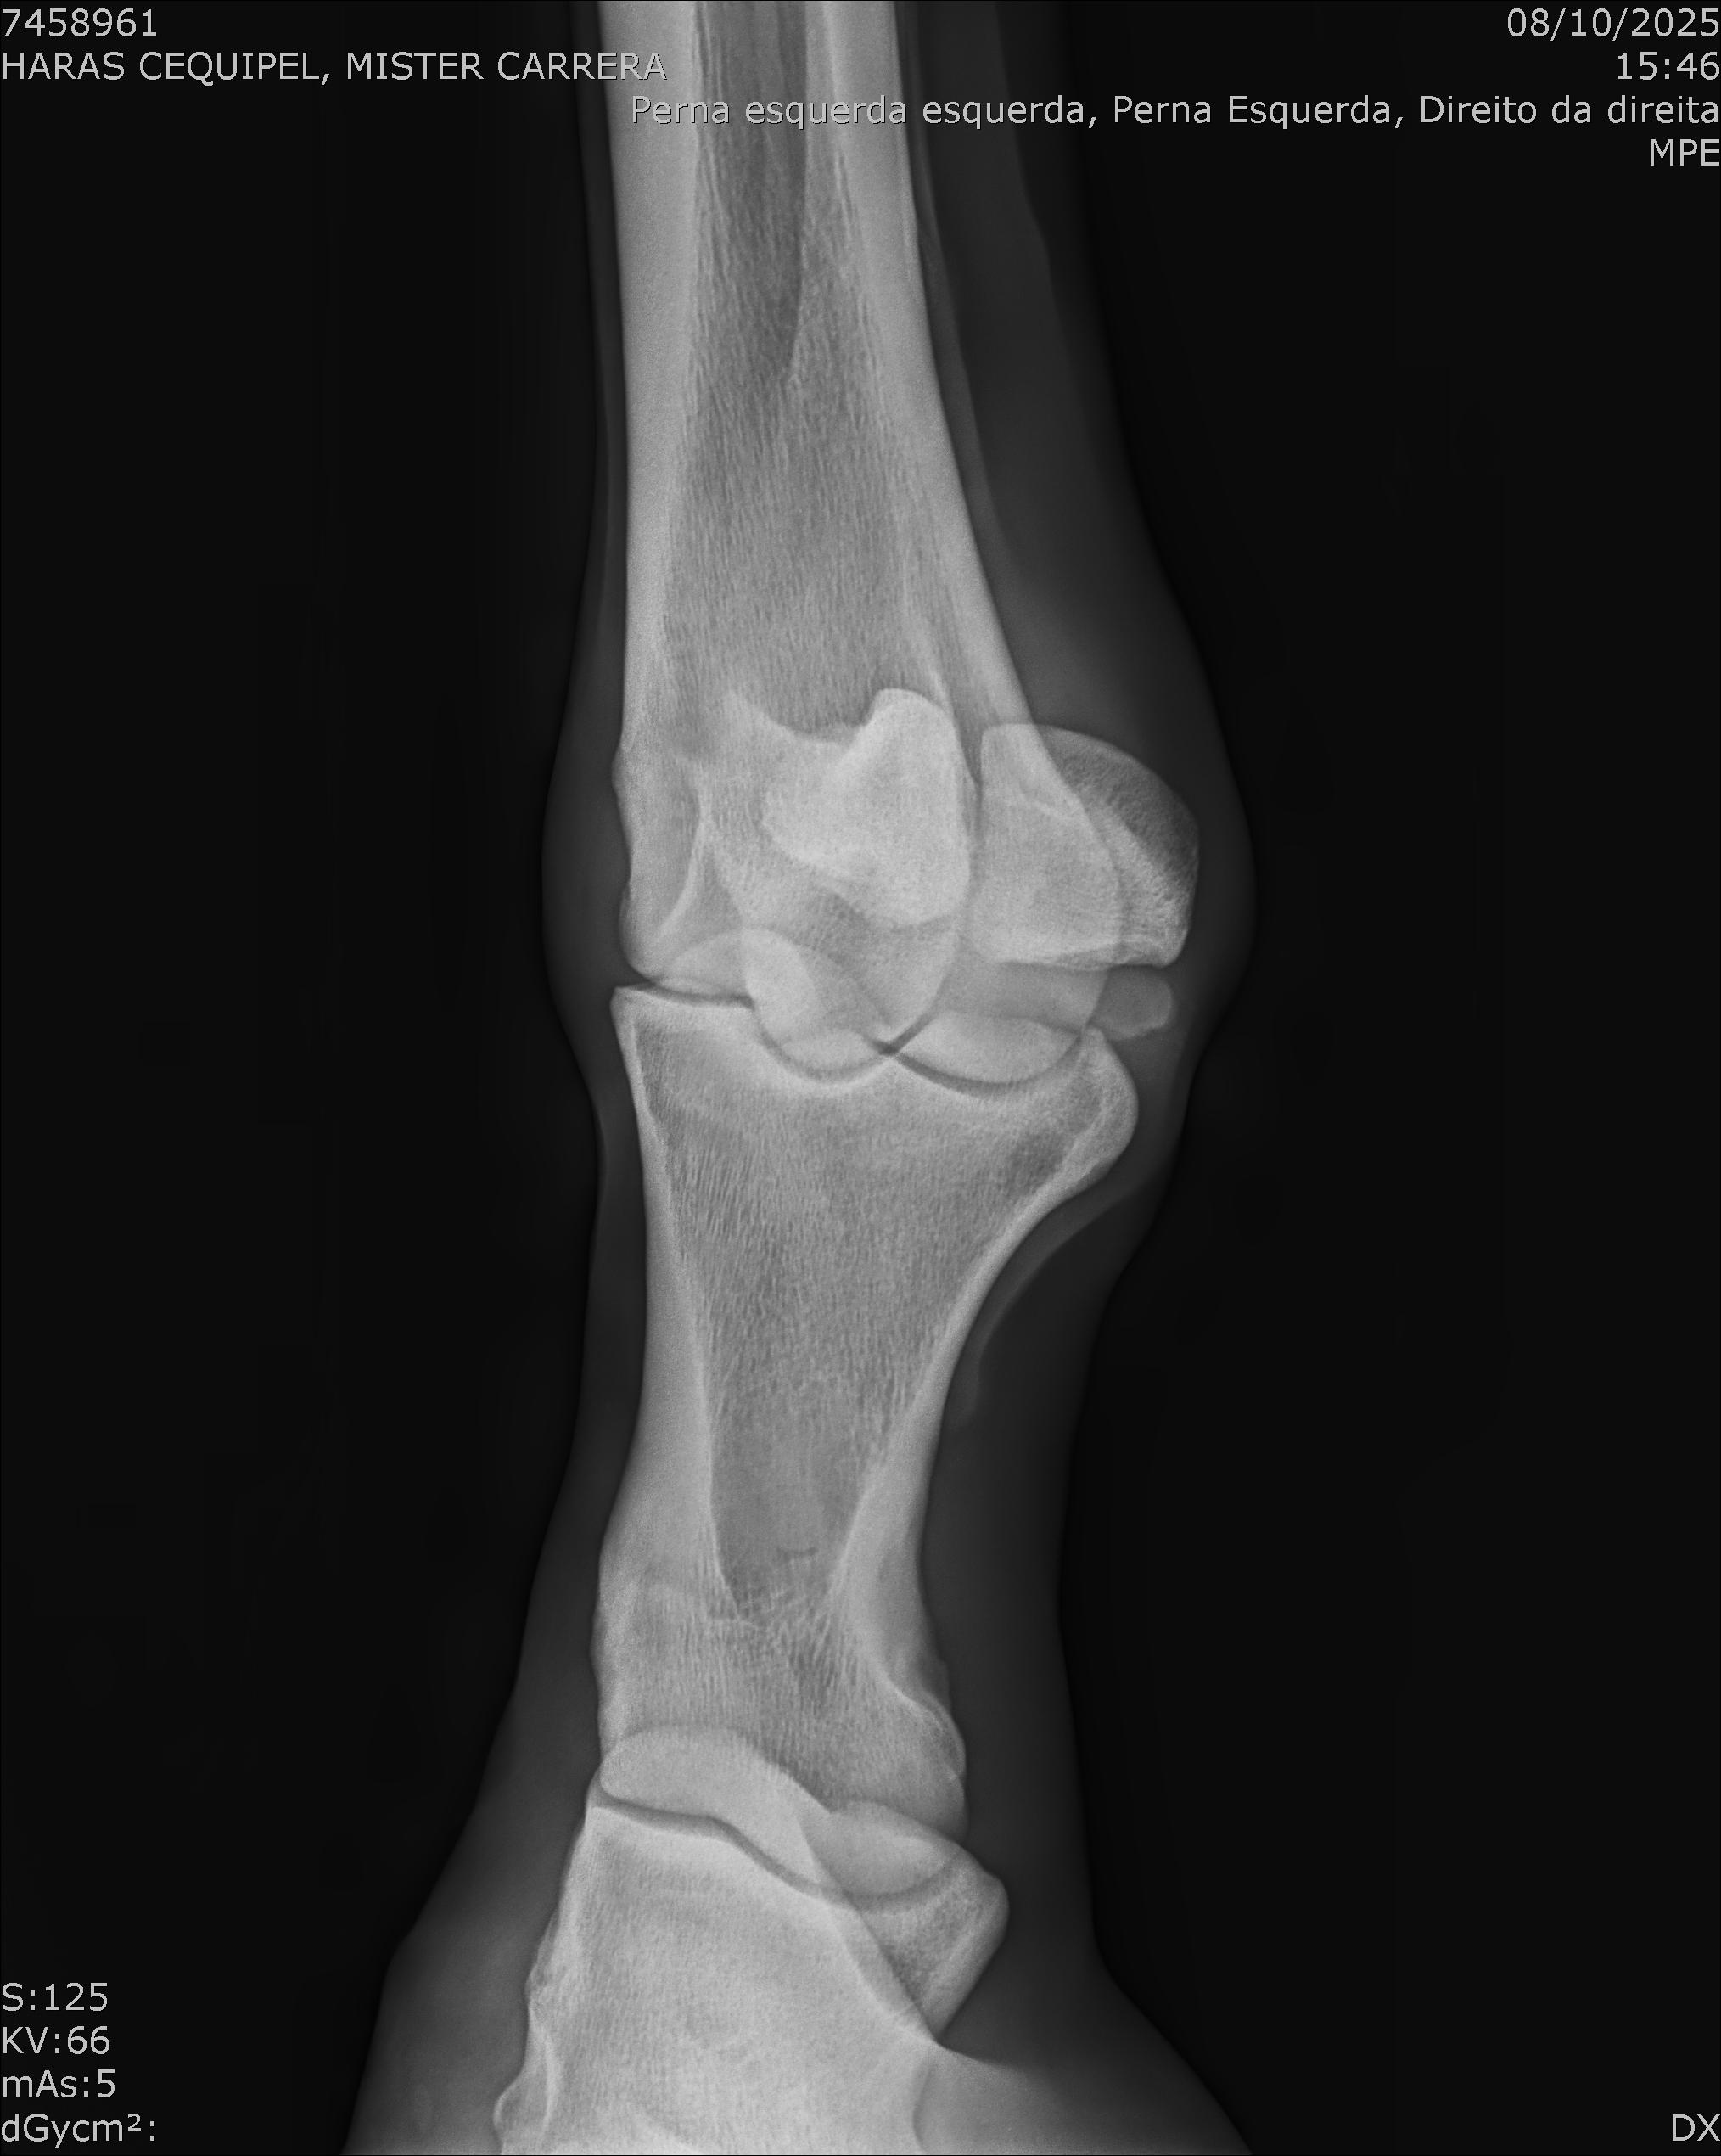

:: RAIOS-X DO LOTE